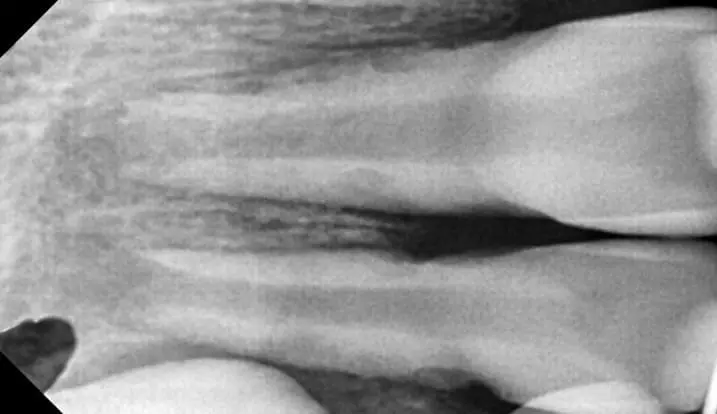

Коли лікар-стоматолог стикається з травмою постійного зуба у дитини, часто необхідно мобілізувати максимум знань і навиків: від реставрації до хірургії. Але найперше - це правильно визначити тактику. Наш курс допоможе відповідним чином приймати рішення в різних клінічних випадках травми постійних зубів у дітей. І не тільки приймати рішення, а і належно їх реалізувати в лікувальну тактику. На детальних клінічних прикладах ми демонструємо належну клінічну тактику та техніки, які часто допомагають врятувати постійні зуби юних пацієнтів.